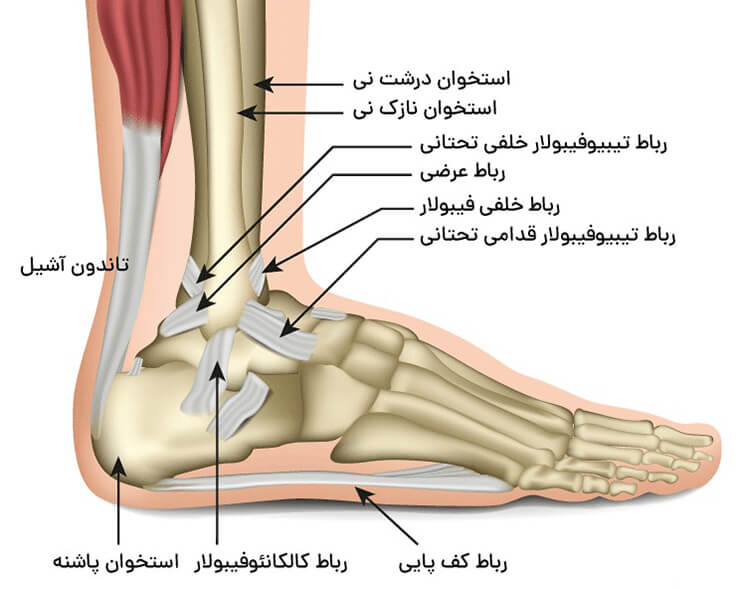

مچ پا (What are the ankle muscles)یکی از مهمترین مفاصل بدن در حرکت، راهرفتن و حفظ تعادل است. هر گامی که برمیداریم، این مفصل باید وزن بدن را تحمل کرده و بهصورت هماهنگ با زانو و لگن حرکت کند. شاید بسیاری از افراد تصور کنند که نقش اصلی در تعادل بر عهده مغز یا گوش داخلی است، اما واقعیت این است که بدون عملکرد صحیح عضلات اطراف مچ پا، حتی سادهترین حرکات مانند ایستادن روی یک پا یا بالا رفتن از پلهها دشوار خواهد شد. در این مقاله به بررسی سه عضله مهم این ناحیه و نقش آنها در تعادل بدن میپردازیم و در ادامه به پرسشهای پرتکرار در این زمینه نیز پاسخ خواهیم داد.

زمانی که بدن میخواهد حالت ایستاده خود را حفظ کند، همیشه مقدار کمی نوسان وجود دارد. این نوسان طبیعی است و توسط سیستمهای عصبی و عضلانی کنترل میشود. یکی از مهمترین این سیستمها، عضلات اطراف مچ پا هستند که مانند طنابهای تثبیتکننده، بدن را در وضعیت پایدار نگه میدارند. نبود قدرت و کنترل کافی در این ناحیه میتواند باعث پیچخوردگیهای مکرر، خستگی زودهنگام، درد و حتی افتادگی قوس کف پا شود.

به همین دلیل، آشنایی با ساختار و عملکرد این عضلات برای ورزشکاران، فیزیوتراپیستها و حتی افراد عادی اهمیت زیادی دارد. در ادامه، سه عضلهای را معرفی میکنیم که بیشترین نقش را در تعادل بدن ایفا میکنند.

۳. عضلات پرونئال (Peroneal Muscles)

این گروه از عضلات در قسمت خارجی ساق پا قرار دارند. آنها مسئول چرخاندن پا به سمت بیرون و جلوگیری از پیچخوردگی به داخل هستند. افرادی که مچ پای آنها مرتب دچار پیچخوردگی میشود، معمولاً ضعف در این عضلات دارند.

ارتباط این عضلات با تعادل کلی بدن